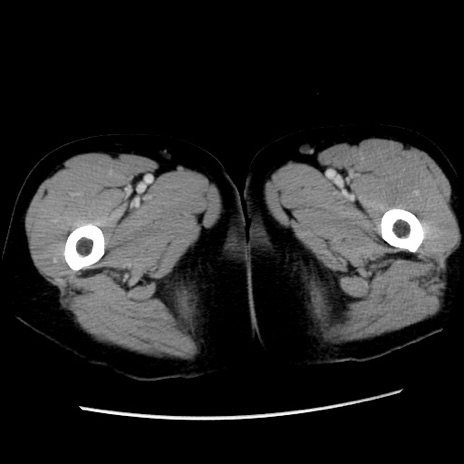

冠状断像

矢状断像